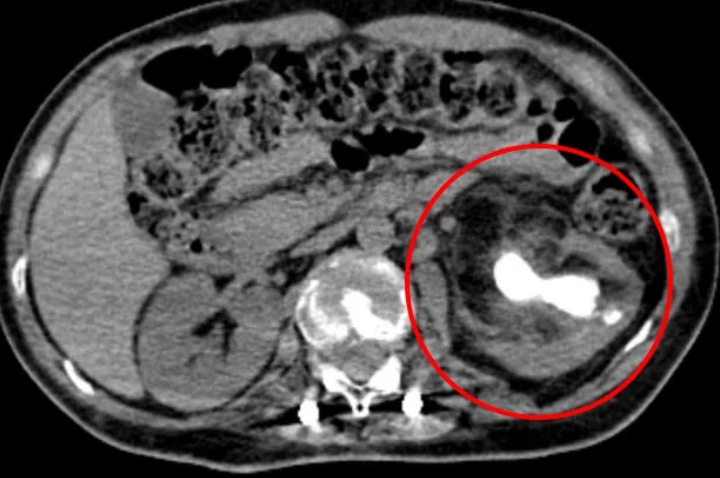

腹部CT检查显示,其左侧肾盂存在巨大结石,且伴有左侧肾盂积水和感染。若不及时处理,肾功能将面临进一步损害的风险。

(左侧肾盂巨大结石伴有左侧肾盂积水和感染)